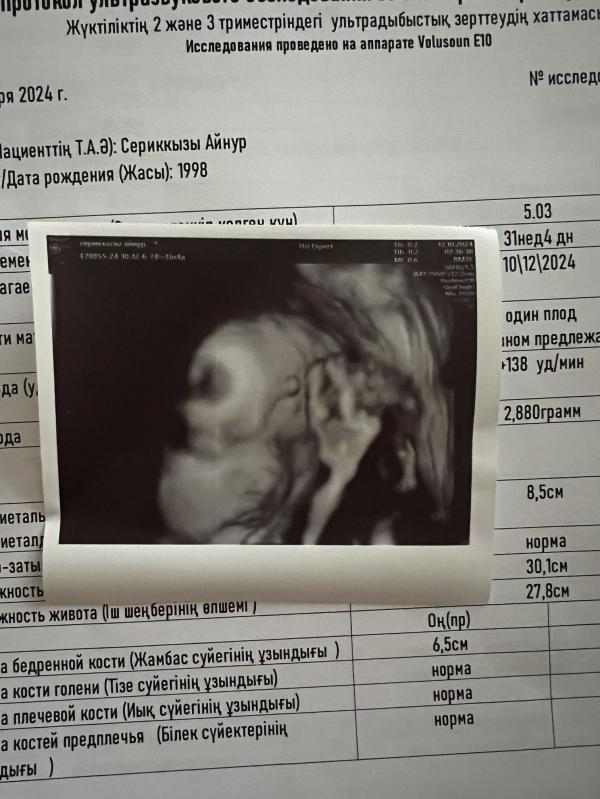

Сходили с мужем на узи к Рудневой. Какая же у нее четкая картинка! Прям все-все видно и понятно. Сыночек всю беременность неохотно показывал лицо, вот и сегодня постоянно держал кулачок у головы. 😂

Я счастливая, лежу, разглядываю снимок и видео, которое снял муж. 🥰